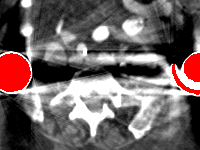

Rating. Table 6 summarizes the ratings and P values for comparison between our model and the other methods. The performance of our model is significantly better than cGan-CT, LI, NMAR, CNNMAR on both datasets (all P values 0.03). Our model also achieves better ratings than DuDoNet.

Visual comparison. Fig. 7 shows two clinical CT images with metal artifacts. Case 1 is with moderate metal artifacts. cGan-CT does not suppress the artifacts completely and generates some fake details. LI, NMAR, CNN-MAR remove all the artifacts but introduce new streak artifacts, which is caused by the discontinuity in the corrected sinogram. DuDoNet outputs over-smoothed sinogram, which leads to blurred tissues close to the metal implants, such as muscle and bone. Only our model can provide realistic enhanced sinogram and remove the artifacts while retaining the structure of nearby tissues. Case 2 is very challenging as the rods bring strong metal shadows and bright artifacts around the vertebra. cGan-CT recovers the shape of vertebra but changes the overall image intensity. Other sinogram inpainting methods fail as the soft tissue and bone near the rods are heavily distorted. Our model removes part of the dark bands and reproduces correct anatomical structures around the rods.

The results show that our model generalizes well for clinical images with unknown metal materials and geometries. We generate simulate training data using titanium and will retrain the model with multiple metal materials to make it more robust. Meanwhile, images with unknown geometry would be processed in the same simulation space. But it is worth noting that our model is limited to 2D geometry and the metal artifacts in 3D projection (e.g. cone-beam CT) are much more challenging.